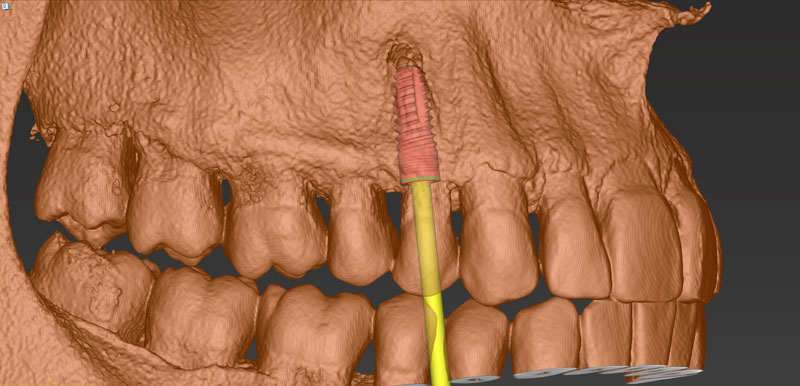

Ψηφιακό πλάνο θεραπείας

Κατευθυνόμενη τοποθέτηση εμφυτευμάτων

Είδη και ακρίβεια χειρουργικού οδηγού

Σχεδιασμός χειρουργικού οδηγού